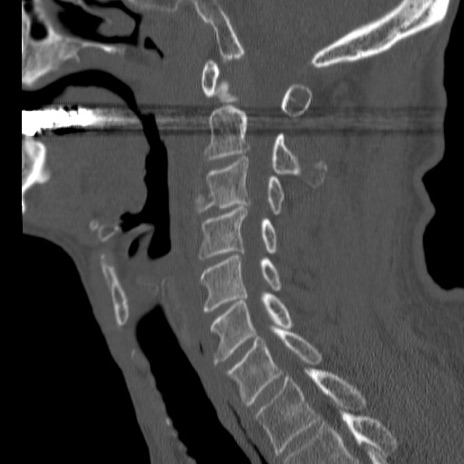

症例46 頚椎CT(矢状断像)

【症例】80歳代男性

【主訴】両側頚部〜上肢のしびれ

【現病歴】昨日、自宅内で転倒、その後より上記症状あり。意識障害なし。

【身体所見】両側上肢のallodynia(熱痛覚過敏)あり。MMTおよびDTRは正確な所見取れず。両上肢の挙上はなんとか可能。

異常所見と診断は?